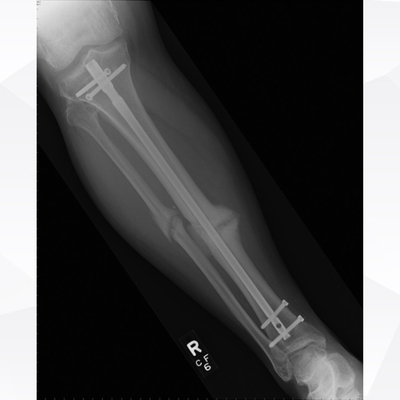

Click on an image below to view more info.